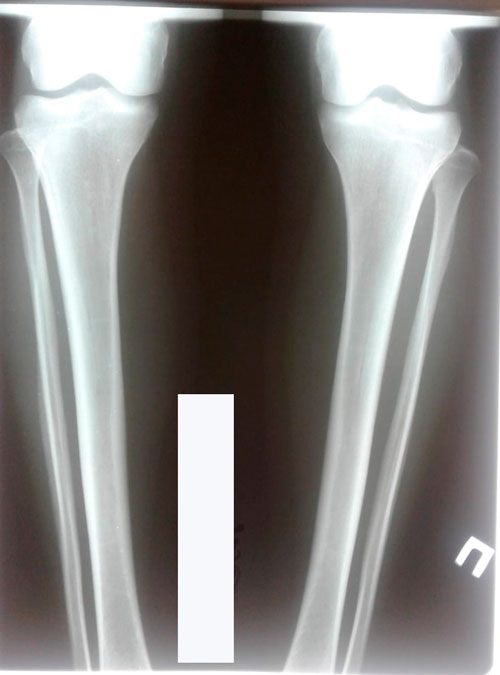

Дата снятия аппаратов 29.08.2018г.

Срок сращения 72 дня.